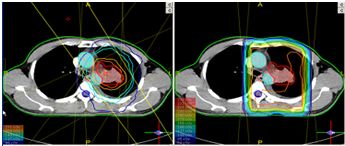

- Tiến hành JO-IMRT 5beams / 33 segments

So sánh 2 đường đồng liều giữa hai kế hoạch xạ trị JO-IMRT (trái) và kế hoạch xạ trị 3D thông thường : Ở kỹ thuật JO-IMRT, đường đồng liều 95% bao sát thể tích cần tia (khối u và hạch), đồng thời tránh được các mạch máu lớn, tuỷ sống và phần phổi lành.

Biểu đồ phân bố liều - thể tích (DVH) so sánh giữa hai kế hoạch: Khối u nhận liều bức xạ 100% giữa 2 kỹ thuật, nhưng ở kỹ thuật JO-IMRT liều bức xạ tại các cơ quan lành thấp hơn rất nhiều so với kế hoạch 3D thông thường.